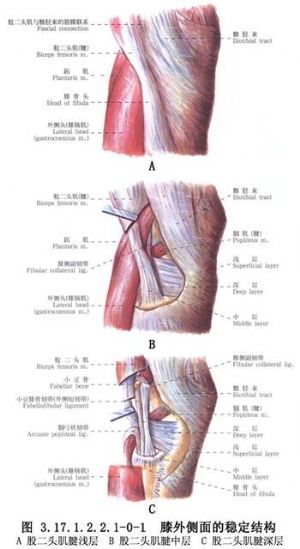

新鮮膝外側副韌帶修補術用於外側副韌帶損傷的手術治療。外側副韌帶對膝關節的穩定沒有內側副韌帶那麼重要,其損傷也較少見,原因是在屈曲位時外側副韌帶鬆弛,不致因旋轉應力受傷,伸膝位時又爲髂脛束、股二頭肌腱、外側關節囊、交叉韌帶所加強,也受到對側肢體保護免受內收位損傷。僅在膝關節輕度屈曲時關節承受內翻應力,可損傷其外側結構,包括髂脛束、外側副韌帶、外側關節囊、膕肌腱、交叉韌帶、股二頭肌、腓腸肌外側頭、腓總神經等(圖3.17.1.2.2.1-0-1~3.17.1.2.2.1-0-3)。

手術相關解剖見下圖(圖3.17.1.2.2.1-1,3.17.1.2.2.1-2)。